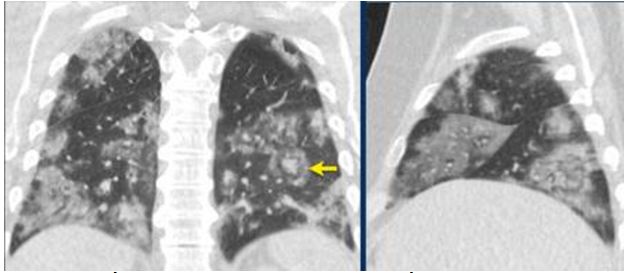

CO-RADS 3: Hình 5 & 6

Hình 5:

Trường hợp 1: Tổn thương GGO bên phải (duy nhất 1 vị trí). PCR (-) với COVID 19

Trường hợp 2: Tổn thương GGO duy nhất phân thùy sau dưới phải (vòng tròn)

Trường hợp 3: Tổn thương GGO duy nhất khu trú phân thùy sau phải (mũi tên)

Trường hợp 4: Tổn thương GGO duy nhất phân thùy sau dưới phải (vòng tròn)

Hình 6:

Trường hợp 5: Tổn thương nhiều ổ đông đặc kết hợp GGO. PCR (-) với COVID 19

Trường hợp 6a & b: Tổn thương đồng đặc cả 2 bên kết hợp GGO lan tỏa (BN Nhiễm cúm A)